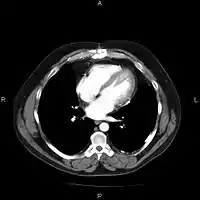

A chest image displayed via a PACS

A full PACS should provide a single point of access for images and their associated data. That is, it should support all digital modalities, in all departments, throughout the organisation.